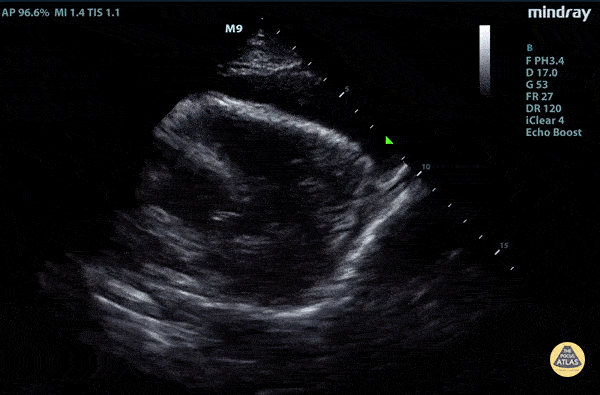

Pericardial Disease - Parasternal Long Type A Aortic Dissection with Tamponade

Elderly fellow who had a headache while bike riding, with some leg weakness. No chest or back pain. Stable for hours then came to hospital, suddenly hypotension and drowsy in ER POCUS RUSH Exam performed lead to rapid diagnosis of Aortic Dissection with tamponade. Right ventricular diastolic collapse can be seen. Claire Heslop - Pediatric Emergency Medicine - University of Toronto Hospital for Sick Children